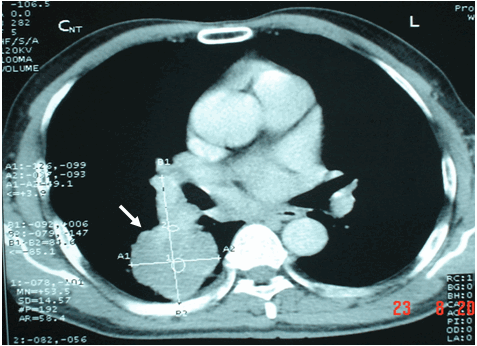

Hình ảnh k phổi thể ngoại vi ở phía sau trên phim chụp CT ngực cùng bệnh nhân